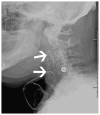

Cross-sectional imaging plays an important role in the evaluation of the retropharyngeal space (RPS) and the prevertebral space (PVS). Because of their deep location within the neck, lesions arising within these spaces are difficult, if not impossible, to evaluate on clinical examination. This article details the cross-sectional anatomy and imaging appearances of primary and secondary diseases involving the RPS and PVS, including metastasis and spread from adjacent spaces. The role of image-guided biopsy is also discussed.